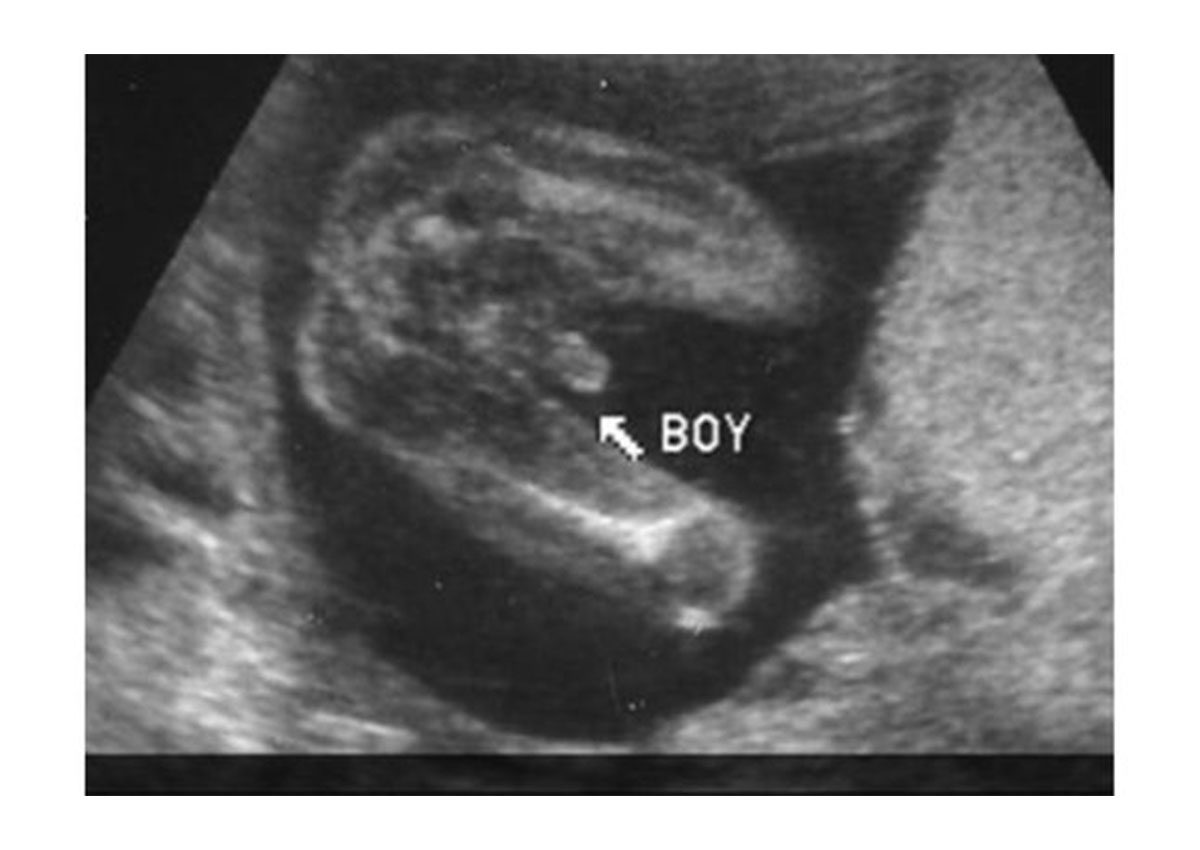

ولتحديد جنس الجنين يتم النظر الى الجهاز التناسلي، فإذا ظهر على الشاشة ثلاث خطوط بيضاء، يدل هذا ان الجنين انثى، أما اذا كان الجنين ذكر، فيُعرف هذا بشكل واضح من العضو التناسلي ومن الكرتان الصغيرتان اللتان تمثلان العضو التناسلي للذكر.

الجنين الذكر